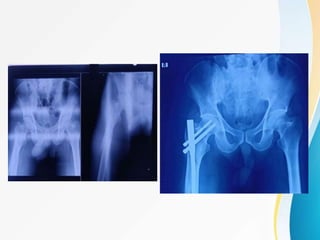

TIP APEX DISTANCE : TAD

• Sum of distances from the tip of the lag screw

to the apex of the femoral head on both the

anteroposterior and lateral radiographic views.

• The sum should be <25mm to minimize the risk

of lag screw cutout .

• TAD > 25 mm , the surgeon should reassess

the fracture reduction and position of Guide

Pin.

TIP APEX DISTANCE :